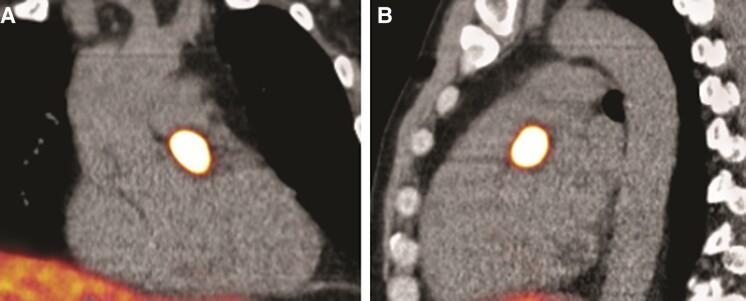

A 44-year-old male with an SDH complex subunit D (SDHD) mutation was diagnosed with an intracardiac paraganglioma attached to the left main coronary artery. Multimodality imaging, including gallium dotatate positron emission tomography computed tomography, cardiac magnetic resonance imaging, and coronary computed tomography angiography (CCTA) confirmed the suspected intracardiac paraganglioma. During follow-up with a CCTA, the mass showed growth, and surgical removal was recommended to anticipate on the risk of compression of the left main coronary artery. Prior to surgery, coronary angiography was performed, which showed no coronary calcifications. The highly vascularized paraganglioma was visible near the left main and proximal left anterior descending artery. The intracardiac paraganglioma was successfully removed through a median sternotomy with cardiopulmonary bypass, without any complications. The post-operative course was uneventful, and histological examination confirmed the diagnosis of a paraganglioma.

一名44岁男性,携带琥珀酸脱氢酶复合体亚基D(SDHD)突变,被诊断患有附着于左冠状动脉主干的心脏内副神经节瘤。多模态成像,包括镓标记奥曲肽正电子发射断层扫描计算机断层扫描、心脏磁共振成像和冠状动脉计算机断层扫描血管造影(CCTA),证实了疑似心脏内副神经节瘤的诊断。在CCTA随访期间,肿块显示生长,建议手术切除以预防左冠状动脉主干受压风险。手术前进行了冠状动脉造影,结果显示无冠状动脉钙化。高度血管化的副神经节瘤在左冠状动脉主干和左前降支近端附近可见。通过正中胸骨切开术并在体外循环下成功切除心脏内副神经节瘤,无任何并发症。术后病程平稳,组织学检查确诊为副神经节瘤。